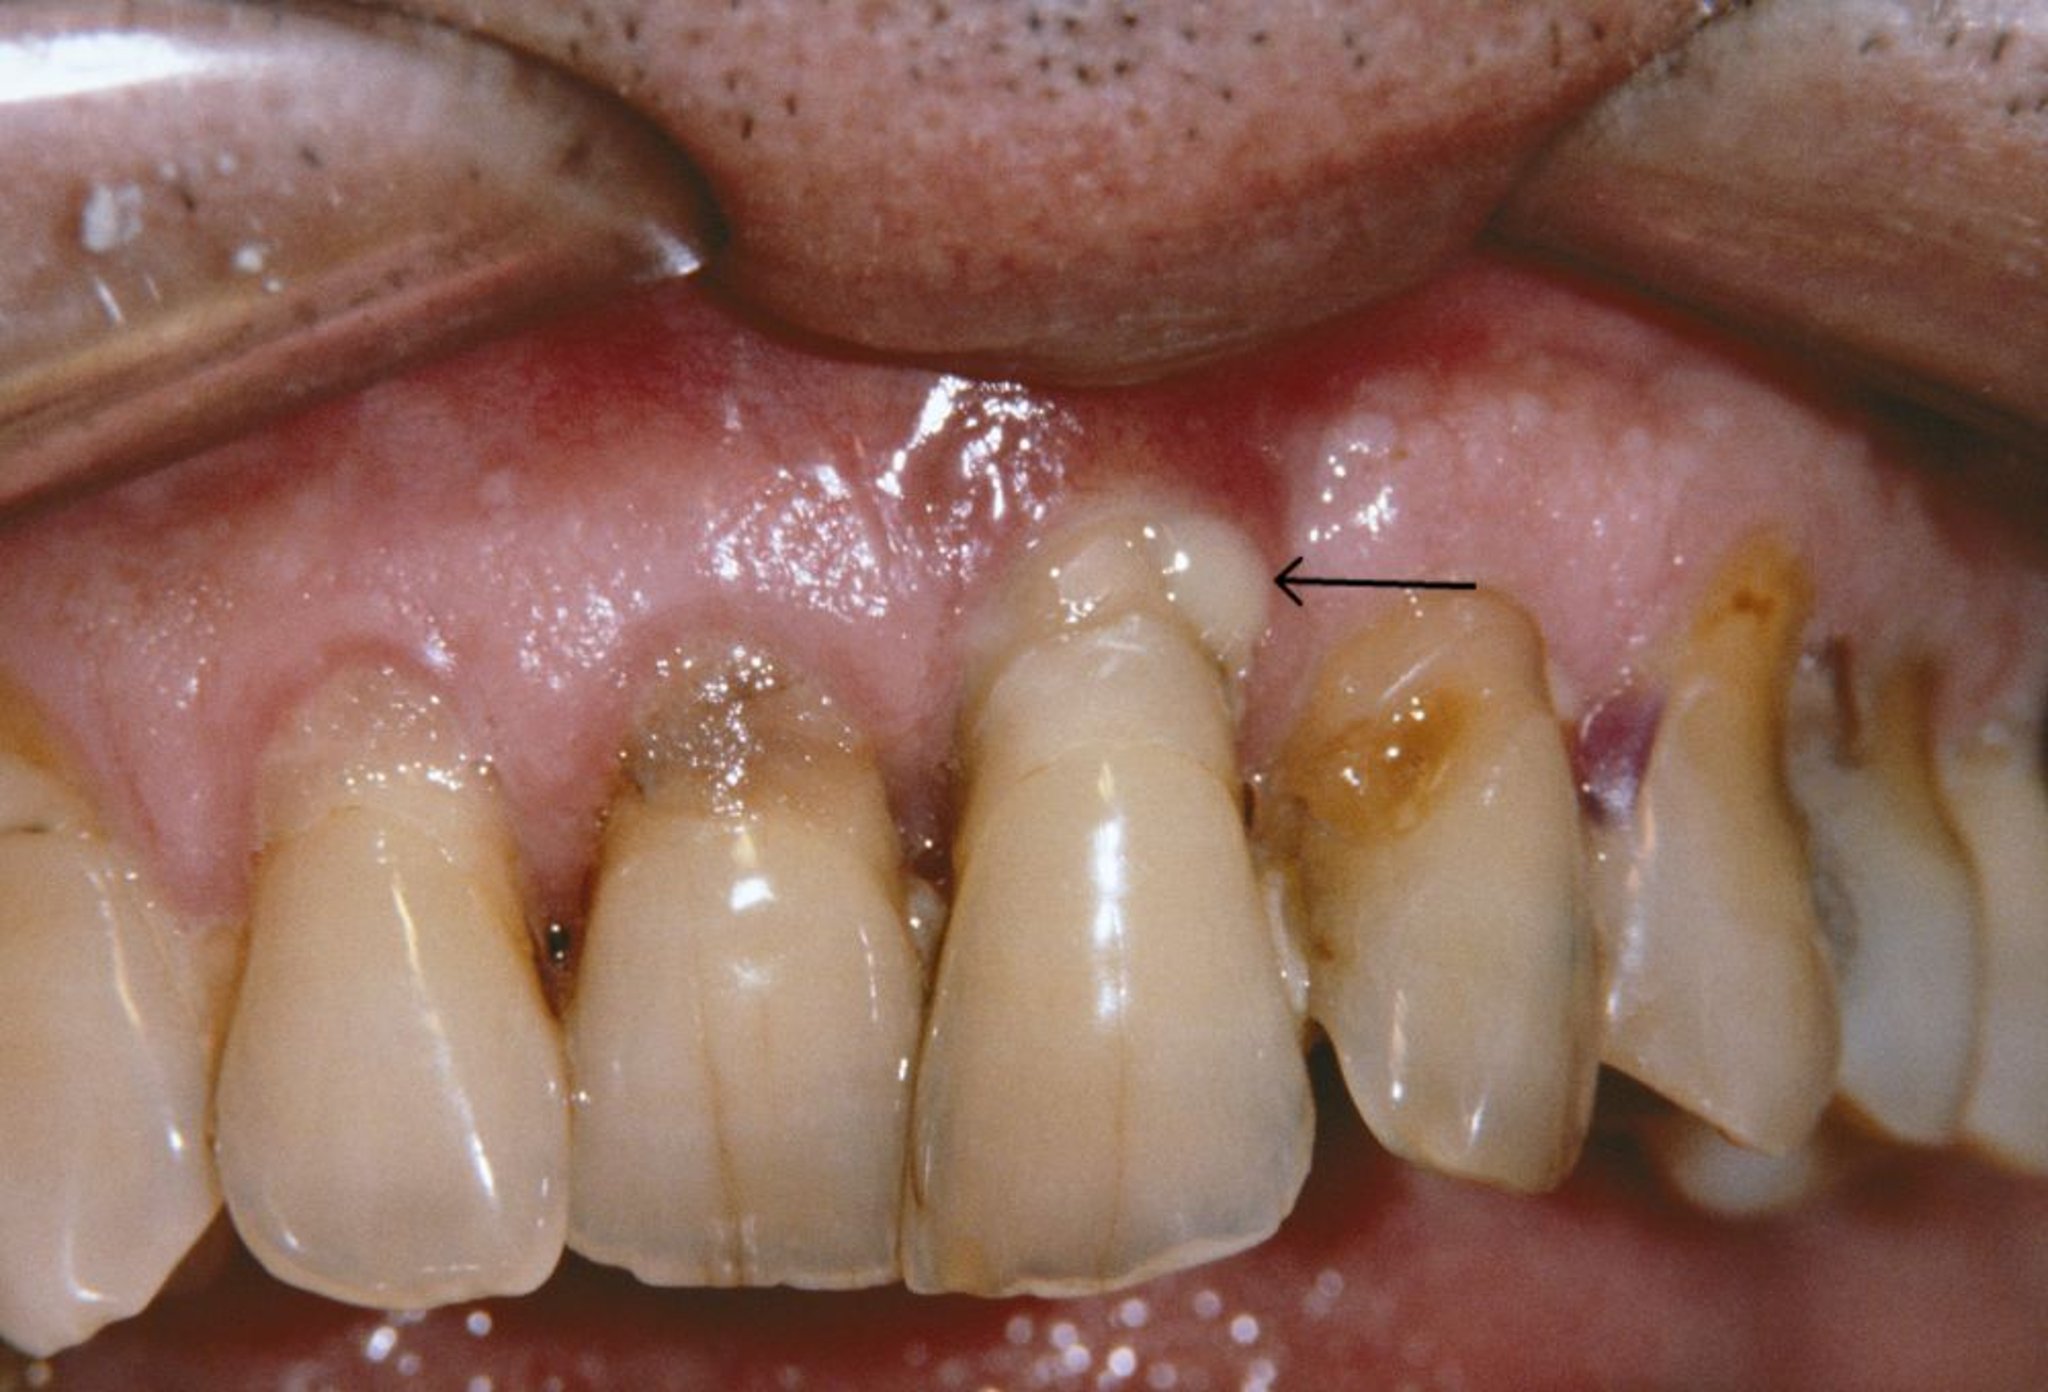

歯周炎

この

写真

しゃしん

には、

ししゅうえん

患者

かんじゃ

の

退縮

たいしゅく

している

歯

は

ぐきと

周

膿瘍

のうよう

(

矢印

やじるし

)が

写

うつ

っています。